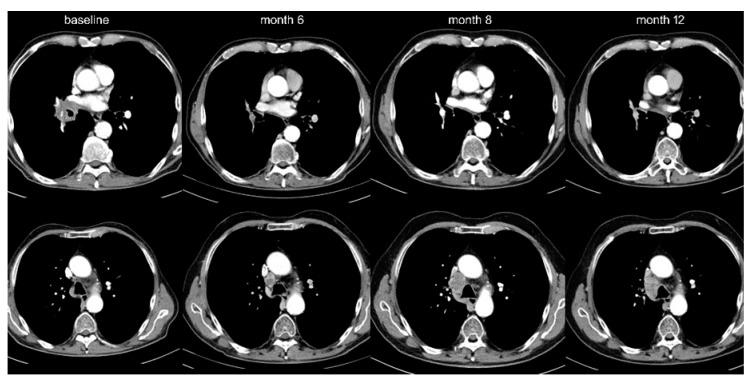

Oligoprogression (OPD) of non-small-cell lung cancer (NSCLC) occurs in approximately half of patients under targeted compounds (TKI) and facilitates use of regional therapies that can prolong survival. In order to characterize OPD in immunotherapy (IO)-treated NSCLC, we analyzed the failure pattern under PD-1/PD-L1 inhibitors ( = 297) or chemoimmunotherapy ( = 75). Under IO monotherapy, OPD was more frequent (20% vs. 10%, < 0.05), occurred later (median 11 vs. 5 months, < 0.01), affected fewer sites (mean 1.1 vs. 1.5, < 0.05), and involved fewer lesions (1.4 vs. 2.3, < 0.05) in the first compared to later lines. Lymph nodes (42%, mainly mediastinal) and the brain (39%) were mostly affected, followed by the lung (24%) and other organs. Compared to multifocal progression, OPD occurred later (11 vs. 4 months, < 0.001) and was associated with longer survival (26 vs. 13 months, < 0.001) and higher tumor PD-L1 expression ( < 0.001). Chemoimmunotherapy showed a similar incidence of OPD as IO monotherapy (13% vs. 11% at 2 years). Local treatments were applied regularly for brain but only in 50% for extracranial lesions. Thus, NSCLC oligoprogression is less common under IO than under TKI, but also favorable. Since its frequency drops later in the disease, regular restaging and multidisciplinary evaluation are essential in order to exploit the full therapeutic potential.

非小细胞肺癌(NSCLC)的寡进展(OPD)约发生在半数接受靶向化合物(TKI)治疗的患者中,这促进了可延长生存期的局部治疗方法的应用。为了明确免疫治疗(IO)的NSCLC中的OPD特征,我们分析了接受PD-1/PD-L1抑制剂(n = 297)或化疗免疫治疗(n = 75)患者的疾病进展模式。在IO单药治疗中,OPD更为常见(20% 对10%,P < 0.05),出现时间更晚(中位时间11个月对5个月,P < 0.01),与后续治疗线相比,在一线治疗中受影响的部位更少(平均1.1个对1.5个,P < 0.05),累及的病灶更少(1.4个对2.3个,P < 0.05)。淋巴结(42%,主要为纵隔淋巴结)和脑(39%)最常受累,其次是肺(24%)和其他器官。与多灶性进展相比,OPD出现时间更晚(11个月对4个月,P < 0.001),且与更长的生存期(26个月对13个月,P < 0.001)和更高的肿瘤PD-L1表达相关(P < 0.001)。化疗免疫治疗的OPD发生率与IO单药治疗相似(2年时为13%对11%)。局部治疗常用于脑转移,但仅50%用于颅外病灶。因此,NSCLC的寡进展在IO治疗下比TKI治疗下更少见,但预后也更好。由于其发生率在疾病后期下降,定期重新分期和多学科评估对于充分发挥治疗潜力至关重要。